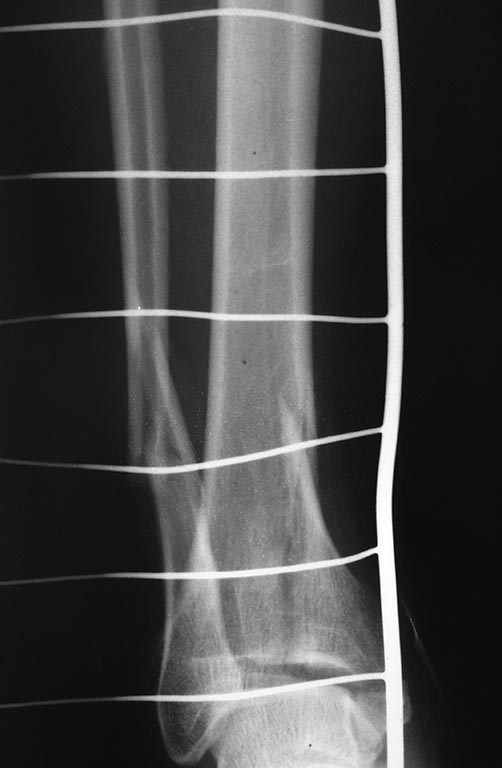

Дмитрий 21 Декабрь 2015, 17:14

Результат операции.

Отправитель: Alexey Semenistyy 22 Декабрь 2015, 00:33

Выглядит вполне себе не плохо. Хотя, кое-что можно было бы сделать по-другому

Отправитель: Alexey Semenistyy 23 Декабрь 2015, 01:39

Дмитрий, моя тактика была ты точно такой же.

1) Даже если бы било чем м с кем, я бы не стал делать окончательный остеосинтез в день поступления. Перелом сложный (44С с претензией быть 43В), больная тучная, значит энергия травмы приличная, несмотря на непрямой ротационный главным образом механизм, и мягкие ткани могут быть скомпроментированы. В первые часы это оценить трудно, можно только предположить. Аккуратная, не грубая закрытая репозиция и наружный фиксатор в положении приблизительной репозиции - это то, что я сделал при поступлении, примерно так же как и вы и это сделали.

2) Я бы все делал в таком же порядке: малоберцовую и задний край, затем медиальный раскол, в последнюю очередь медиальную лодыжку. Оценка стабильности синдесмоза.

КТ, безусловно, показана, но только после репозиции и в аппарате

Иначе я бы поступил с направлением некоторых винтов, с их функцией (см вложение):

1)Винты, фиксирующие задний край, должны быть стягивающими, приходить перпендикулярно плоскости перелома.

2)Нужен хотя бы один стягивающий винт вне или через опорную пластину для вертикального метаэпифизарного раскола параллельно суставной поверхности (в прямой проекции) и достаточно близко к ней.

3) Винт через внутреннюю лодыжку также должен быть стягивающим. Направление и длину его я бы выбрал такое, чтобы он заканчивался не в зоне вертикального разлома, не в зоне перехода метафиза в диафиз, где в центре кости уже мало губчатого вещества, а более дистльно и вертикально , где "губка" более плотная. Возможно, стягивание петлей по Веберу здесь более предпочтительно.. Ну и с открытой репозицией медиальной лодыжки постарался бы...

3) В качестве опорной пластины для медиального раскола взял бы 1/3-трубки, ну в крайнем случае максимум 3,5 метафизарную LCP. "Ложка" тут избыточна, а вот стягивающего винта не хватает.

Отправитель: Paul 24 Декабрь 2015, 08:09

На ренгенограмме в сагитальной проекции контуры кортикальной пластинки внутренней лодыжки не совпадают - в месте перелома, а на сагитальной проекции, кажется, смещение внутренней лодыжки кпереди....

Re: Травма голеностопного сустава 44С3 помогите определиться с оперативной тактикой

сергей 28 Декабрь 2015, 19:52

Интересно бы сделать снимки обоих голеностопов на одной кассете и посмотреть синдесмоз на здоровой конечности. Какое-то ощущение, что имеется небольшой подвывих...